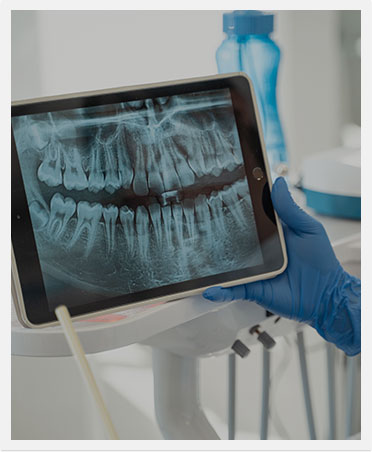

Advanced Technology